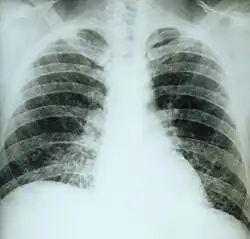

This chest film shows diffuse pulmonary infiltration due to acute pulmonary histoplasmosis caused by H. capsulatum.

Primary pulmonary histoplasmosis is caused by inhalation of Histoplasma capsulatum spores, and approximately 10% of people with this acute infection develop erythema nodosum.[1]: 316